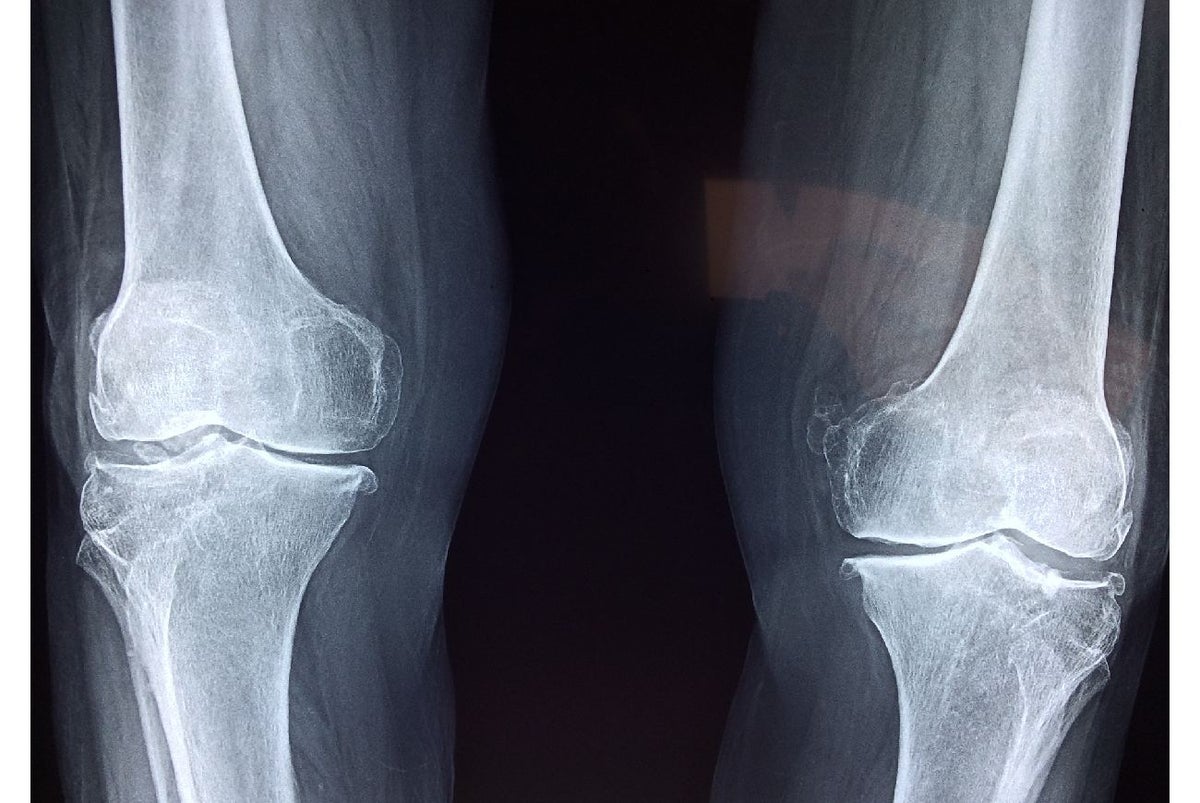

Según la Organización Mundial de la Salud la osteoporosis es una enfermedad que se caracteriza por la disminución de masa ósea, causando un incremento en la fragilidad y debilidad del hueso, las personas que la padecen son más susceptibles a sufrir algún tipo de fractura. La gran mayoría de personas alcanza una densidad ósea alrededor de los 30 años, luego de esta edad la renovación continúa, pero de una manera menor.

Los tres tipos de osteoporosis más comunes son: Osteoporosis postmenopáusica, la cual se presenta en mujeres mayores de 45 años y sucede por la falta de estrógenos que deja de producir la mujer; Osteoporosis senil, esta es la más común y se da por la pérdida de masa ósea a causa de la edad y, por último, la Osteoporosis corticoidea que se da por el consumo de algunos medicamentos y es inducida por glucocorticoides (compuesto que pertenece al tipo de los llamados esteroides).